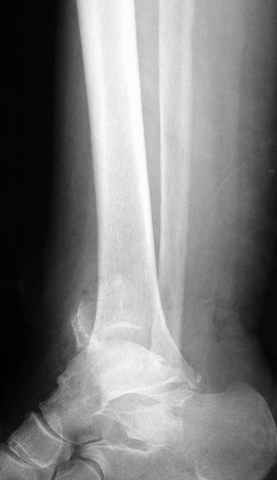

Pilon fracture:

-Появляется ориентир и остов, на чем можно строить восстановление, почему сперва малоберцовую, впервые обьяснили и описали (Pylon type and Ankle fractures) в середине 50х Rienau и Gay.

Восстановливая длину и ротацию малоберцовой кости, затем относительно легче произвести реставрацию остальных элементов перелома дистального эпиметафиза болшеберцовой кости.

конец малоберцевой кости, к нему прикрепляется латеральный суставной фрагмент дистального эпиметафиза большеберцовой кости (как на снимке)

и таранная кость, которые при репозиции малоберцовой кости репонируются автоматически.

Из работ Ramsey and Hamilton, Yablon et., укорочения на 1мм

малоберцовой кости, уменьшает на 42% контактную поверхность между

малоберцевой и таранной кости, которое в свою очередь приводит к

увеличению давления на остальные части суставной поверхности, что

является предпосылкой раннего артроза.